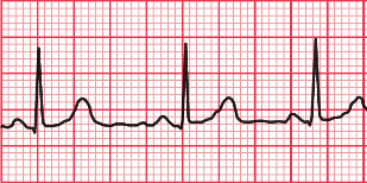

La electrocardiografía es el estudio de las oscilaciones de voltaje que sufre el miocardio durante el ciclo cardíaco. Estas

oscilaciones pueden registrarse desde la superficie corporal mediante un aparato denominado electrocardiógrafo, obteniéndose un registro gráfico que se llama electrocardiograma.

El electrocardiógrafo cuenta con un dispositivo inscriptor que es una aguja inscriptora que se desplaza, hacia arriba cuando se detectan potenciales positivos y hacia abajo cuando los potenciales detectados son negativos, dibujando una serie de ondas sobre un papel milimetrado que se desplaza a una velocidad constante de 25 mm/s. El papel se divide en cuadrados grandes, cada uno de 5 mm de ancho y equivalente a 0,2 s. Cada cuadrado grande tiene cinco cuadrados pequeños de ancho, y cada cuadrado pequeño tiene 1 mm de ancho y equivale a 0,04 s.